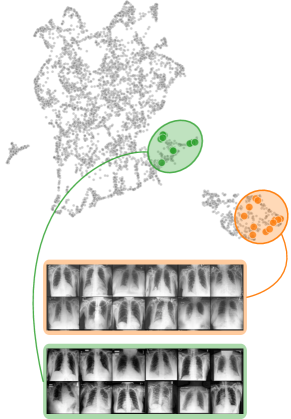

Data Perspective

We first apply SpRAy in input and latent space, computing input feature importance scores using LRP summed over color channels. To obtain latent relevances, we use intermediate relevance scores in the LRP computation process after the (out of four) residual block, max-pooling over spatial dimensions to yield relevance scores for layer with channels. The clustering of pairwise cosine distances between heatmaps is shown in Fig. 6 (top left). Detected outlier clusters contain samples with spatially coherent biases, e.g., the black circle around the lesions originating from microscopes (). In contrast, clustering latent relevance scores reveals more complex, less spatially dependent clusters, as shown in Fig. 6 (top right), including the ruler artifact () and the microscope (). Compared to those in input space, the cluster for the microscope in latent space represents a more diverse high-level concept. In the input space visualization, we further highlight samples from the ruler cluster detected in latent space. Instead of forming a cluster, they spread across the entire embedding space, indicating that the bias is too complex to be detected in input space.

Next, we apply bias identification approaches from the model perspective by identifying outlier neurons based on activation pattern via DORA and relevance pattern by clustering pair-wise cosine distances between concept relevance scores. We focus on latent activations and relevances after the third residual block. DORA uses a distance function based on how neurons activate upon each others n-AMS, achieving high similarity when neurons activate upon similar input signal. A 2D visualization of the resulting distance matrix is shown in Fig. 6 (bottom left). Identified outlier concepts include ruler () and (white) hair (). We further compute pairwise cosine distances between latent relevance scores , aggregated over spatial dimensions, and apply UMAP to embed the resulting distance matrix in . This results in high similarity between neurons (concepts) that the model uses similarly for predictions. The concept clustering is visualized in Fig. 6 (bottom right), highlighting two outlier clusters focused on rulers () and blueish tint ().